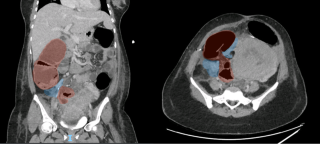

A 31-year-old previously healthy woman, with no surgical history, presented with sudden-onset, severe peri-umbilical abdominal pain unresponsive to high-dose opioids. CT-scan revealed mildly dilated distal jejunum with mesenteric edema and free fluid (Fig. 1, 2). Because of persistent pain despite step III analgesia, emergency diagnostic laparoscopy was performed. Intraoperatively, a closed-loop obstruction of an ileal segment was identified, herniated through a narrow internal window formed by an adherent mesenteric vessel supplying a Meckel’s diverticulum (Fig. 3). The vascular band was divided, releasing the closed loop, with no irreversible small bowel ischemic damage. The Meckel’s diverticulum was resected. The post-operative course was uneventful, and the patient was discharged after two days.